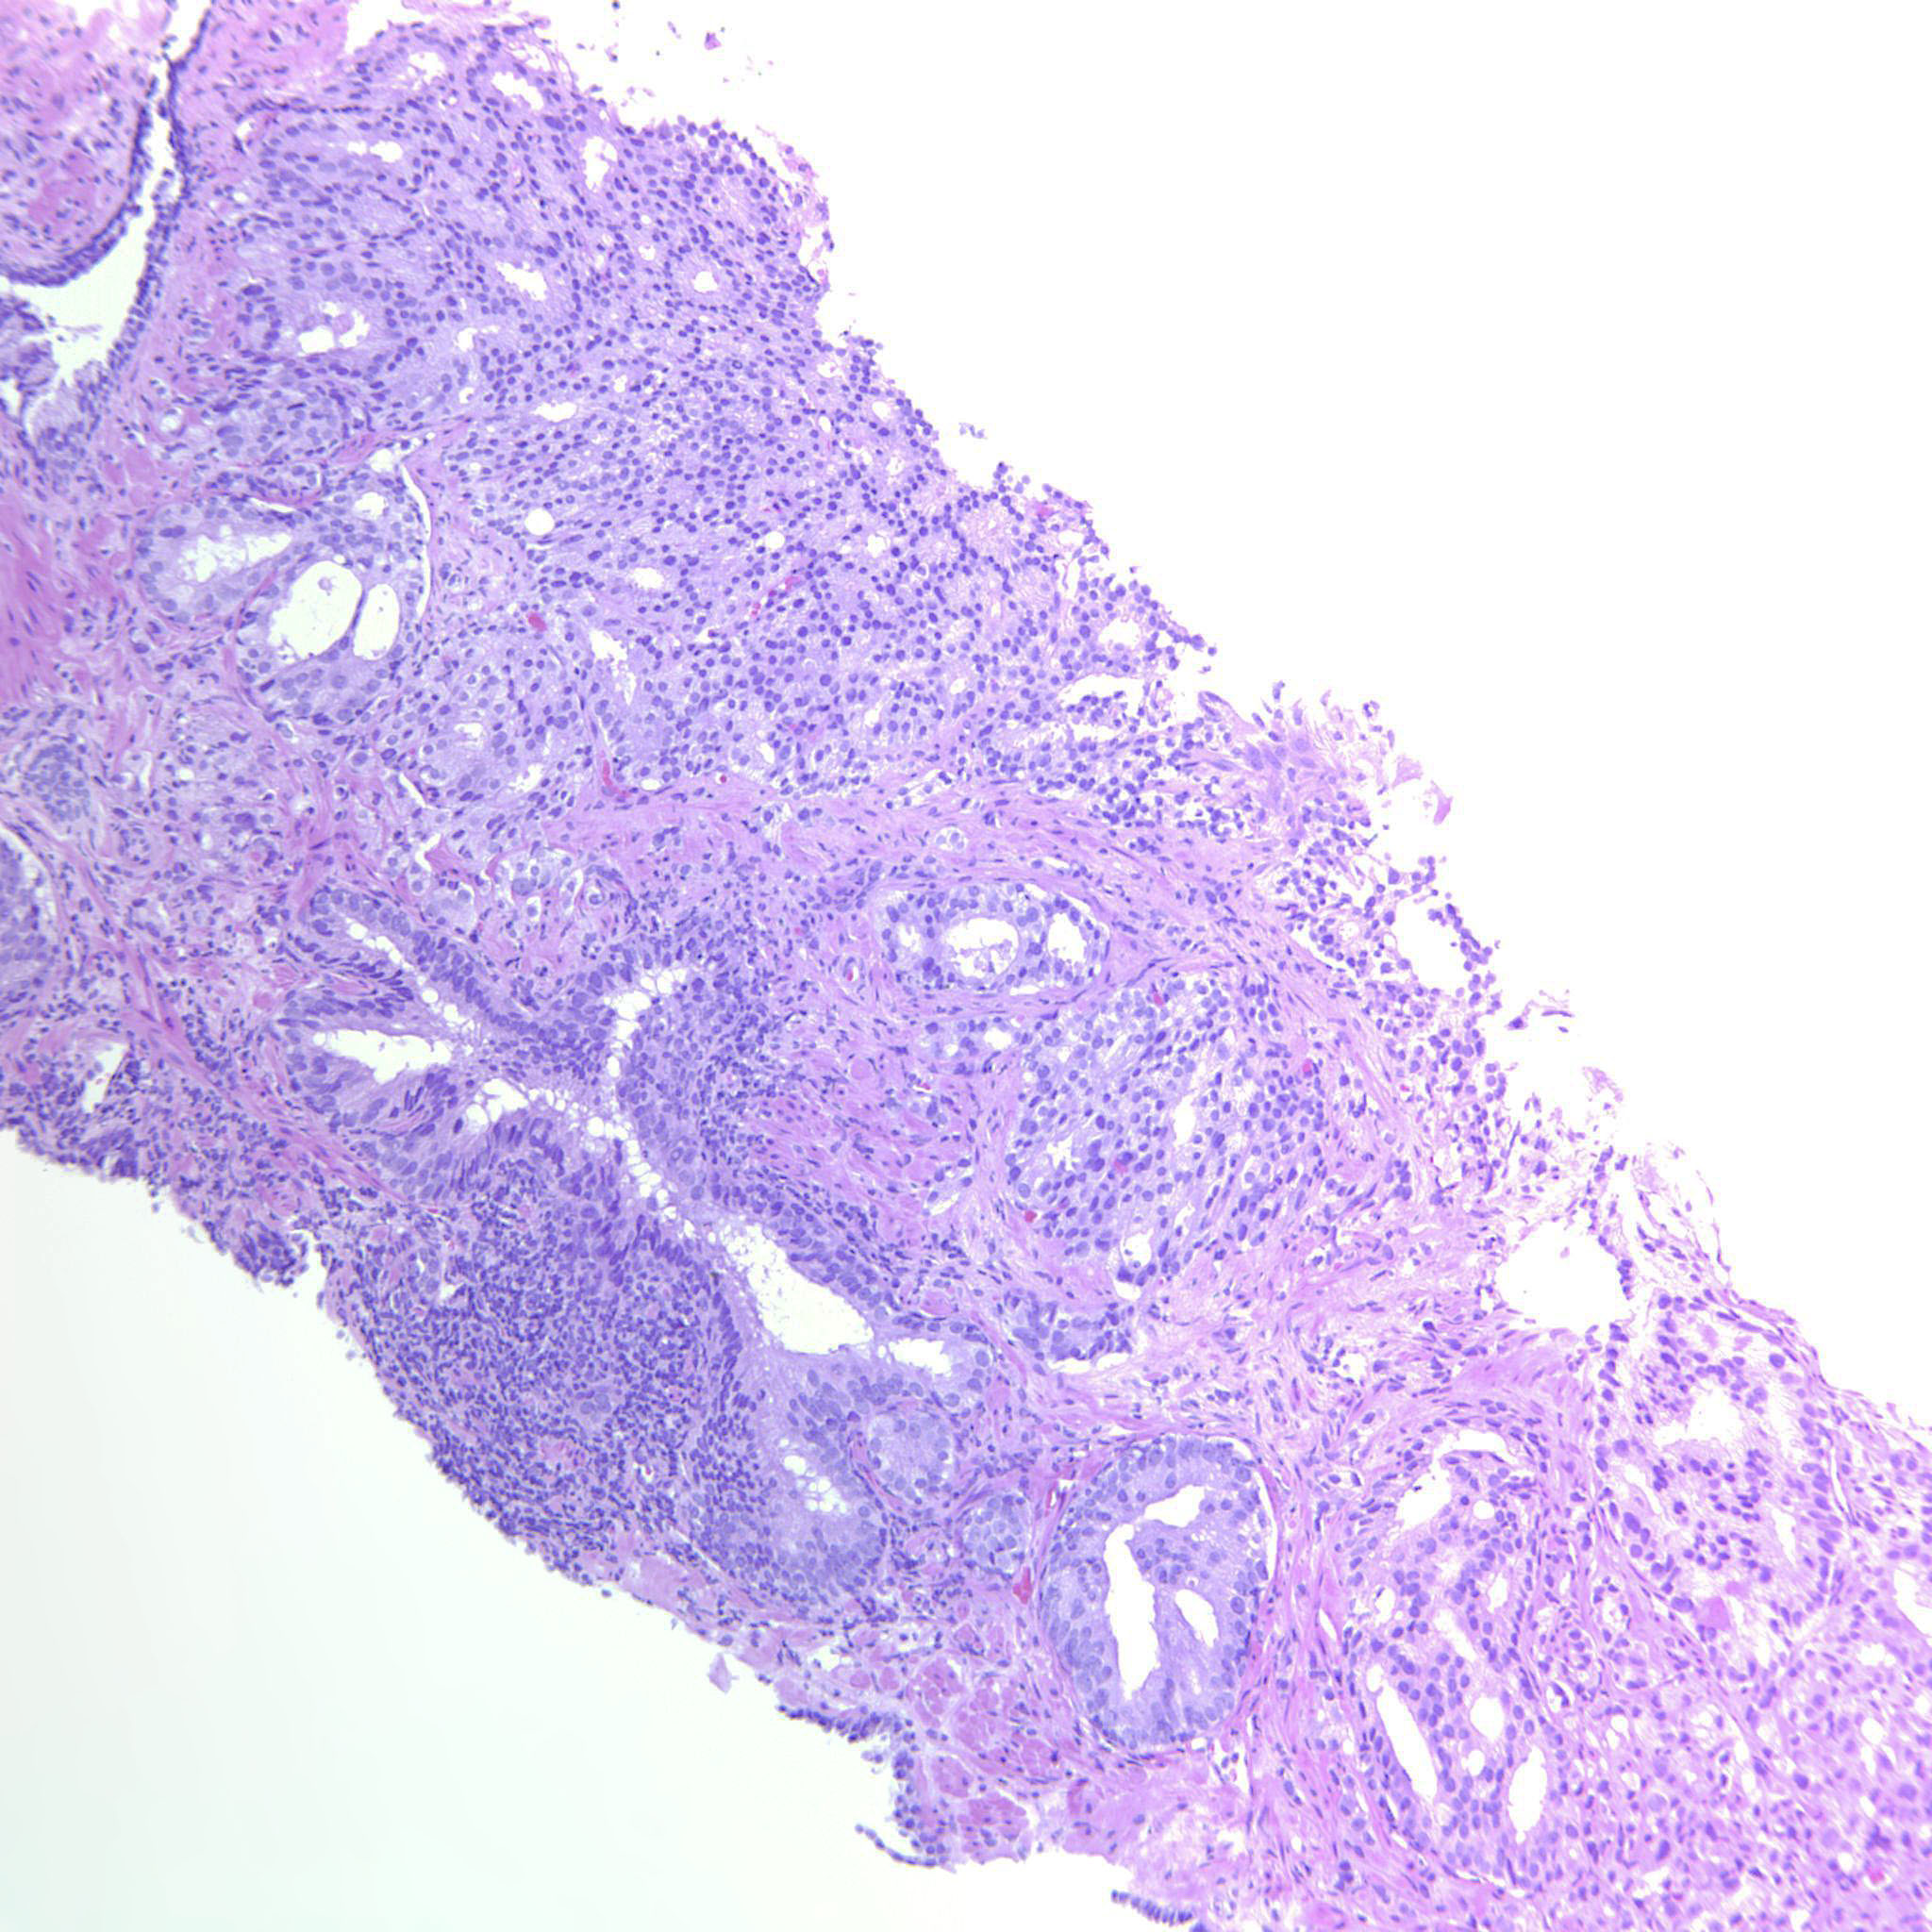

Consensus grade: GS 4+4=8 (ISUP 4)

Case description (by case creator):

Large cribriform sheets and also tightly packed poorly formed glands. Some seem to be solid nests or single cells but not convincing for GP5.